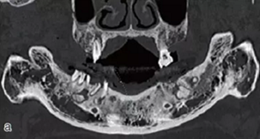

術(shù)前拍攝錐形束CT,進(jìn)行三維重建和種植方案規(guī)劃。從CT圖像中可以看出頜骨內(nèi)有骨島和殘根,為避免種植體植入骨島區(qū),考慮在兩側(cè)頦孔區(qū)種植4~5顆種植體,采用套筒冠進(jìn)行即刻修復(fù)。從重建的結(jié)果中可知前牙區(qū)牙槽嵴呈刀刃狀。種植方案為:對前牙區(qū)牙槽嵴進(jìn)行截骨修整,并在兩頦孔之間的區(qū)域內(nèi)植入5顆種植體。

圖15 種植方案的規(guī)劃:a.患者的CT圖像的截面圖,圈紅處為骨島;b.患者摘掉活動義齒后的下頜;c.患者上下頜骨的CT三維重建;d.下頜骨截骨后模擬植入5顆種植體